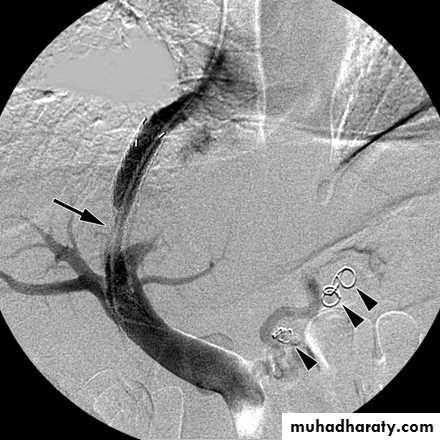

• TIPSS (Transjugular intrahepatic portosystemic stent shunt)

Transjugular intrahepatic portosystemic shunt (TIPS) procedure because of variceal bleeding unresponsive to pharmacologic and endoscopic treatment. Portogram shows clearly visible narrow segment (arrow) of portosystemic shunt. Coils (arrowheads) placed to occlude esophageal varices.